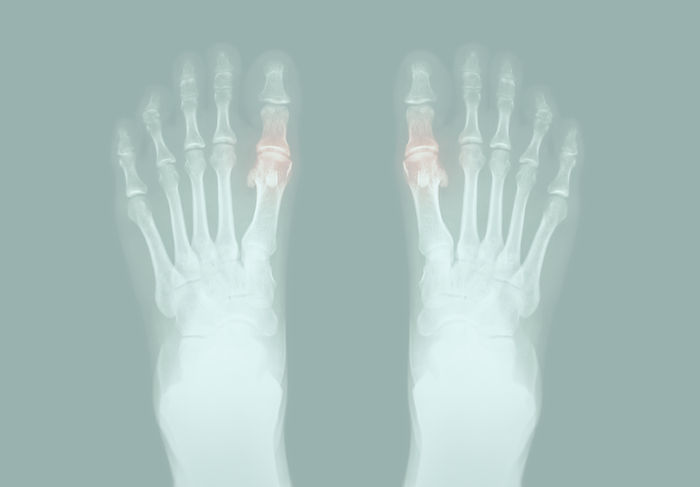

Gout is a painful inflammatory arthritis caused by high uric acid levels, resulting in crystal buildup in joints It typically manifests as sudden, severe pain, swelling, and redness, primarily in the big toe but can affect other joints. If not managed, gout may lead to chronic pain and joint damage. Beyond joint pain, research has shown that gout can be a warning sign for other serious health conditions, including cardiovascular disease and diabetes. Early and specialized care is essential to protect your overall health.